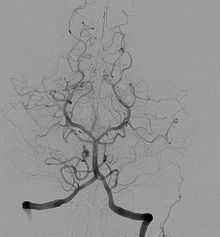

Neste dia o médico e professor, Egas Moniz, realizou a primeira angiografia cerebral com sucesso num doente vivo.

Esta técnica inventada por ele mereceu a sua nomeação para o Prémio Nobel da Medicina por quatro vezes, que finalmente viria a ganhar em 1949 pela descoberta da leucotomia pré-frontal.